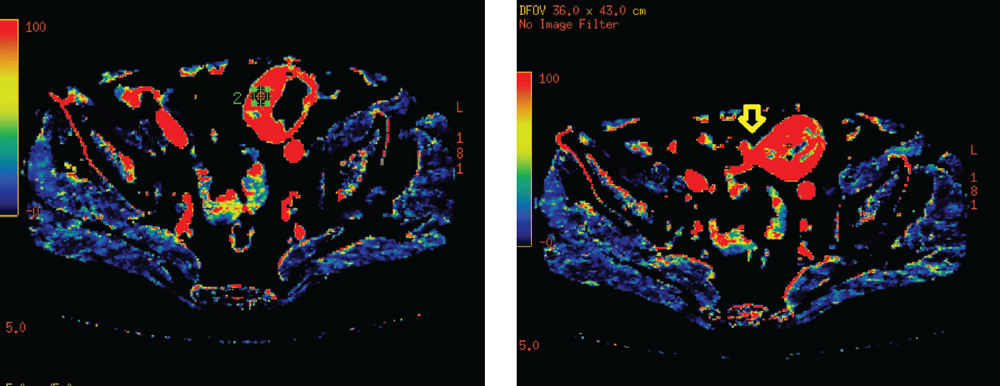

В выявлении ПФВ существенную роль играла спиральная компьютерная томография (СКТ). При СКТ отмечалось утолщение стенки кишки с неравномерным, достаточно часто циркулярным сужением просвета соответствующего участка (рис. 3).

Рис. 3 Спиральная компьютерная томография. Местнораспространенная опухоль сигмовидной кишки, осложненная перифокальным воспалением

Fig. 3. SCT: a locally advanced swelling of the sigmoid colon, complicated by perifocal inflammation

СКТ позволяла определить степень местного распространения опухоли на соседние органы и ткани, наличие воспалительных изменений в окружающей клетчатке. Появление газа в параколярной клетчатке свидетельствовало о формировании параканкрозного абсцесса или перфорации опухоли. Кроме того, СКТ помогала составить представление о поражении лимфатических узлов и отдаленном метастазировании.